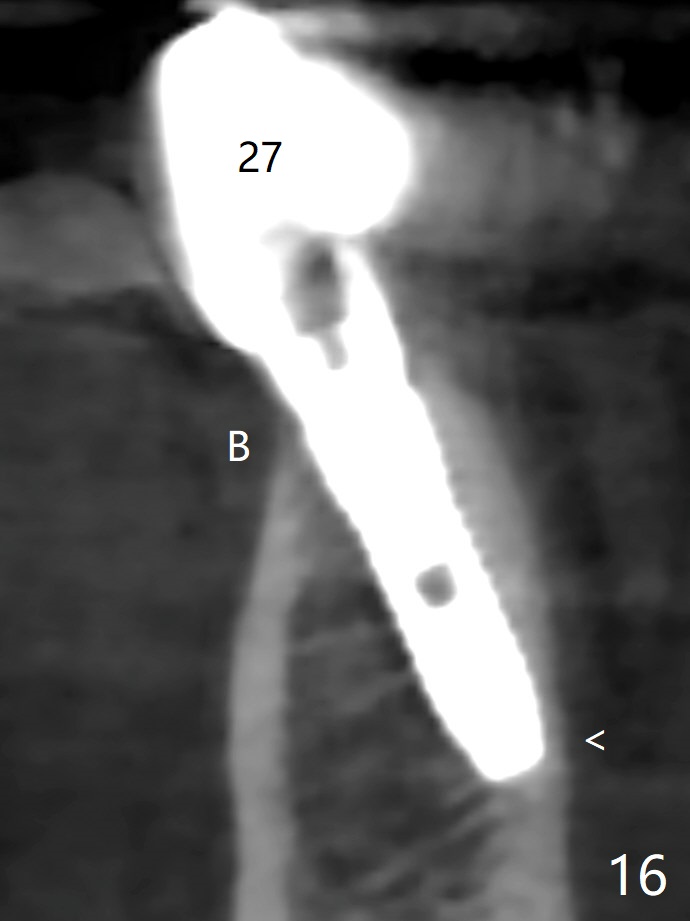

The mesial defect at #27 appears to have been repaired 8 months postop (Fig.8,9 *); there is no bone loss at 1-piece implant sites. The gingival recession seems to remain the same before and after removal of the provisional FPD (Fig.10,11). The bulging abutment at the cervix is less prominent when a straight abutment is used and prepared (Fig.12, 4.5x5.5(5) mm). There is no bone loss at #23, 25 and 27 sites 2.5 years post cementation (Fig.12-15), although the trajectory of the implants could be improved by using surgical guide (Fig.16-18).